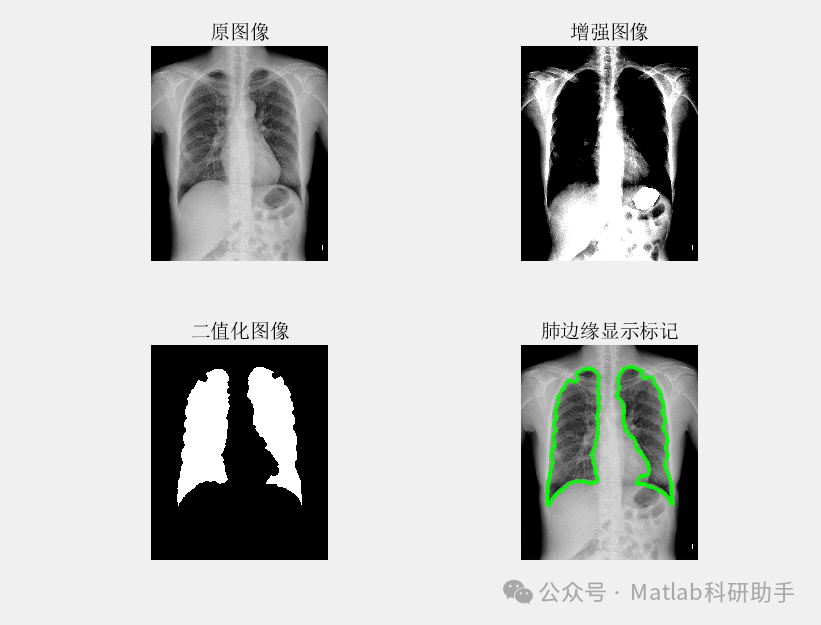

基于最小误差法的胸片分割系统,通常采用深度学习模型,如U-Net或其变体,作为核心分割引擎。该模型通过大量标注数据进行训练,学习从胸片图像到肺部区域掩膜的映射关系。其核心思想是最小化模型预测的分割结果与真实标注之间的误差,从而实现准确的分割。

具体的训练过程中,常用的损失函数包括Dice Loss和Binary Cross Entropy Loss等。Dice Loss关注分割区域的重叠度,更适用于解决类别不平衡问题。Binary Cross Entropy Loss则逐像素地比较预测概率和真实标签,适用于像素级别的分割任务。通过选择合适的损失函数并优化模型参数,能够有效降低分割误差,提高分割精度。

基于最小误差法的胸片分割系统具有以下优势:首先,它能够自动学习图像特征,避免了人工设计的局限性。其次,该系统在大量数据训练下,能够表现出较强的鲁棒性和泛化能力。最后,其分割精度较高,为后续的疾病诊断提供可靠的基础。